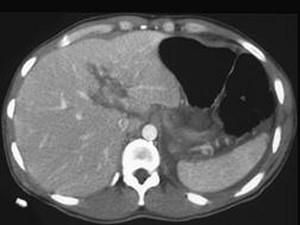

男,42岁,肝区钝器伤后2小时,CT扫描如图,最可能的诊断是 ( )A、脂肪肝B、肝内胆管扩张C、肝淋巴管瘤D、肝挫裂伤E、肝胆管细胞癌

问题 男,42岁,肝区钝器伤后2小时,CT扫描如图,最可能的诊断是 ( )

选项 A、脂肪肝 B、肝内胆管扩张 C、肝淋巴管瘤 D、肝挫裂伤 E、肝胆管细胞癌

答案 D